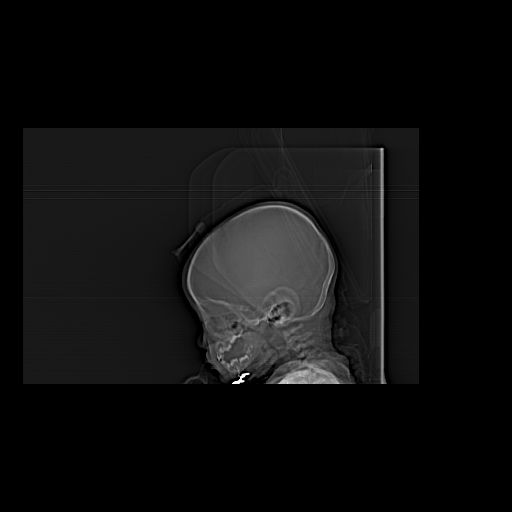

男,10月,足月剖腹产,无缺氧病史,当时评分均正常,学走路时脚后跟不着地!

小孩子片子,看得少,请各位老师看看有问题没?